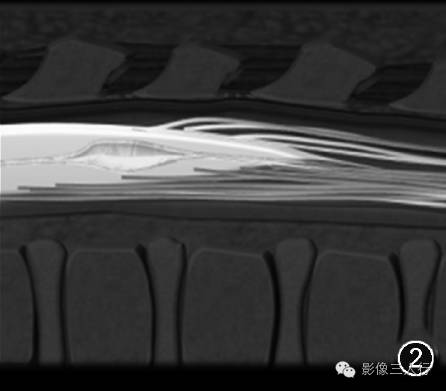

图1~3 男,5 d。超声矢状切面显示第五脑室是位于脊髓圆锥内且囊壁光滑的囊腔(图1,↑);图2为图1的示意图;矢状面T2WI显示第五脑室是位于脊髓圆锥中央的囊性扩张结构,囊内呈高信号(图3,↑)